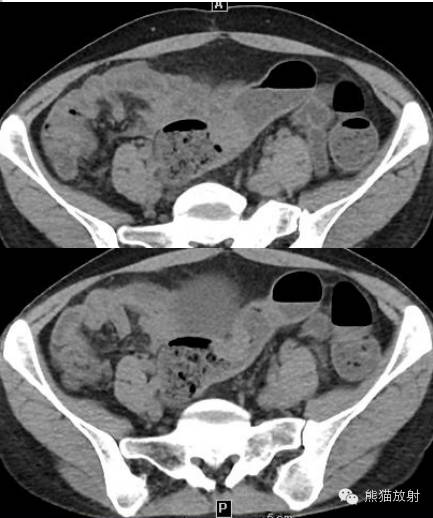

女,39岁,下腹部阵发性疼痛2月余,大便次数增多,为粘液便,无便血、黑便。后患者腹痛反复发作,大便频繁。14余年前行剖宫产手术。

结肠镜检查:乙状结肠远端(距肛门约20cm)见粘膜广基隆起,表面充血、糜烂,周围粘膜蛇皮样变,至肠腔狭窄,取活检4块。病理示:(乙状结肠)粘膜糜烂性活动性炎症伴固有腺增生及灶性淋巴组织增生。

超声内镜检查:距肛门20cm见2.0cm的隆起,表面粘膜粗糙、糜烂。病灶呈低回声,内回声均质,边界清,大小约2.1*1.4cm,起源于固有肌层。

术后病理:(乙状结肠)子宫内膜异位症。

肠子宫内膜异位症

诸病灶分别如下图中圆圈所示: